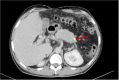

Methods: This was a retrospective cohort study of patients with NCPH who underwent PSRS between 2014-2020 in JIPMER, Puducherry, India. CP was performed in patients with a long tail of pancreas, with the tip of pancreatic tail extending up to splenic hilum on preoperative CT. Perioperative parameters and shunt patency rate of patients who underwent PSRS with CP (Group A) were compared with patients undergoing conventional PSRS (Group B). Statistical analysis was performed using the Mann-Whitney U test and χ2 test.

Results: Eighty four patients with NCPH underwent PSRS (extrahepatic portal vein obstruction = 39; noncirrhotic portal fibrosis = 45). Blood loss was lower (p = 0.002) and post-shunt fall in portal pressure higher (p = 0.002) in Group A. Shunt thrombosis rate was lower (p = 0.04) while rate of complete variceal regression (p = 0.03) and biochemical pancreatic leak (p = 0.01) were higher in Group A.There was no clinically relevant pancreatic fistula in either group.